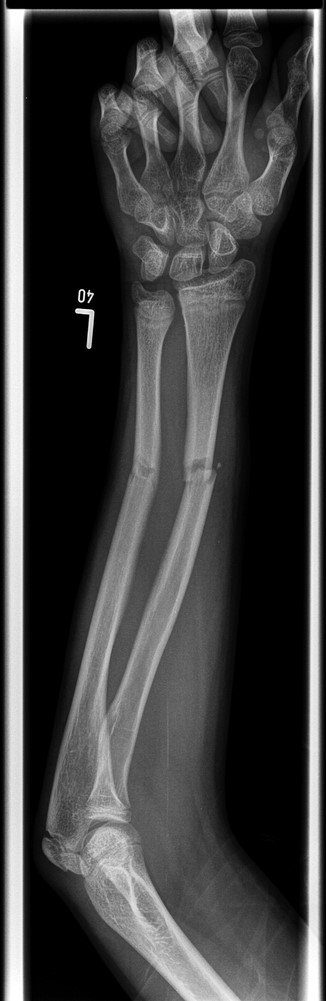

A 12-year-old male patient sustained a closed midshaft both-bone forearm fracture of their non-dominant arm from a fall on a trampoline (Figs 1 and 2). Anatomical reduction was achieved with a manipulation under anaesthesia (MUA), but it was noticed that there was a mechanical block to extension of the ring finger. The radius and ulna were therefore approached through separate incisions and it was discovered that the FDP was entrapped at the ulna fracture at the level of the musculotendinous junction. Following release the fingers regained a full range of motion and the patient went on to heal without further complication (Figs 3 and 4).

Pre-operative anteroposterior (AP) radiograph showing level of fracture at the junction of proximal two-thirds and distal one-third.